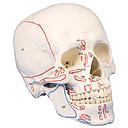

Modèle anatomique - Crâne humain avec marquage insertions et origines musculaires

Modèle anatomique - Crâne humain en trois (3) pièces avec le marquage des insertions et des origines musculaires.